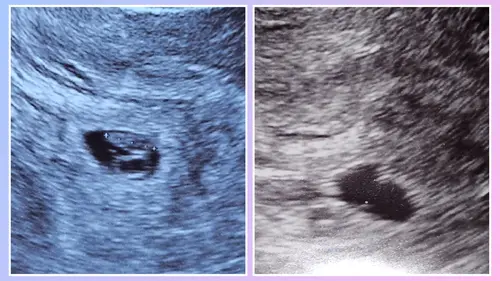

Het verschil in echo's waarbij ze aangaf dat het hetzelfde was als haar collega. Rechts met 6+1 en links met 7.0

Ja klopt maar vind het zelf zo raar dat ze dan nu zegt dat het niet gegroeid is ten opzichte van de eerste echo terwijl ze ook zei dat er geen meting was gedaan en wijzelf zonder echoscopische ervaring heel duidelijk verschil zagen. Bij de eerste echo was het echt alles klein, hartje twijfel, niet meetbaar, niet op de foto te krijgen. En nu was het zo duidelijk allemaal zonder enige moeite. Ze bracht de camera in en *plop.. hartje in beeld. Direct. Dat vind ik zo raar. Ze zegt er is geen groei ten opzichte van vorige week terwijl het voor onszelf zo overduidelijk gegroeid leek te zijn en er vorige week helemaal geen meting is gedaan en ze ook zei dat ze geen echo foto's opslaan dus die kunnen ze niet terugkijken.

Ja vorige week bij de echo was ik volgens de berekening 6+1 dat heeft ze niet nagemeten. Dat weet ik 100% zeker. Vandaag was de berekening 6.2/6.4 (2 metingen) en zei ze dat het ten opzichte van vorige week (6.1) niet gegroeid was. Maar wie zegt dat er vorige week niet al een speling van een dag of 3 inzat? Het was zo super pril toen en ze heeft niet gemeten. Dan zou de echo van vandaag dus wel gewoon kloppen.

Ik zou idd, wat je in je eigen bericht al zegt zelf een echo boeken op eigen kosten en kijken wat die meting zegt en of het overeen komt met je bevindingen. Het is ook echt mm werk en als ik je foto bekijk, zie ik een duidelijk verschil. Er is nieteens een verschil meetbaar, als er de eerste keer niet gemeten is.